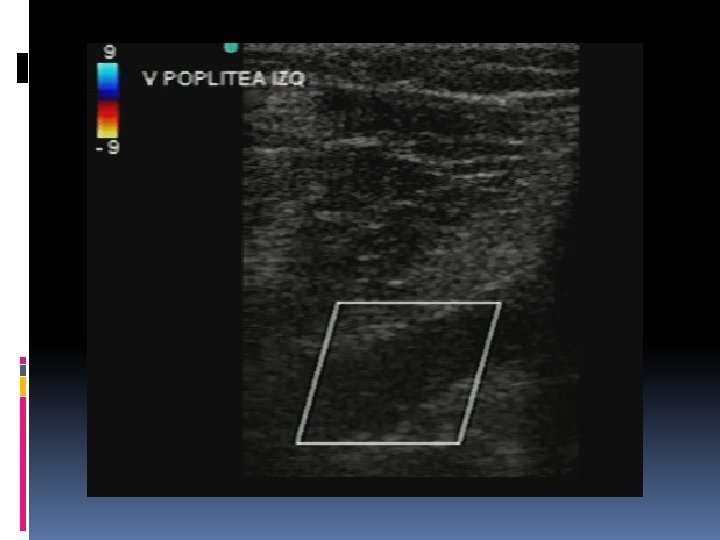

Estudio ecográfico. El objetivo del Doppler venoso es confirmar la permeabilidad vascular, identificar el tipo de insuficiencia venosa (profunda, superficial y/o de comunicantes), determinar los puntos de reflujo/entrada y realizar el mapeo venoso (expresión gráfica del estudio).

Criterios de diágnóstico de reflujo anormal en la venas De acuerdo consenso de la Unión internacional de Flebología publicado en las Guías de Manejo del Foro Venoso Americano, los criterios actuales son: Reflujo mayor de 1 segundo para la vena femoral y poplítea. Reflujo mayor de 0. 5 segundos para las demás venas del sistema venoso profundo y para todas las venas del sistema venoso superficial. Reflujo mayor de 0. 5 seg y diámetro mayor de 0. 35 cm para las venas perforantes, con la precaución que sólo se deben considerarse a tratar aquellas venas perforantes que se encuentren cercanas a una úlcera cicatrizada o activa; es decir, pacientes en estadío C 5 y C 6 de la clasificación de CEAP. Dr. Álvaro Cruz Mézquita.